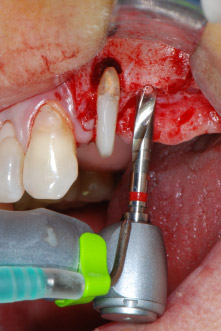

Les lits implantaires ont été préparés sur les sites 25 et 26 à l'aide d'instruments rotatifs, utilisés dans un contre-angle avec un rapport de transmission 20:1 avec un nouveau moteur d'implantologie puissant (Implantmed, W&H) (Fig. 8).

Le lit implantaire a été préparé à l'aide d'un nouveau moteur d'implantologie (Fig. 20), en combinaison avec un contre-angle spécialement conçu pour la chirurgie orale et l'implantologie.

Grâce à un rapport de transmission de 20:1, ainsi qu'au couple élevé du moteur d'implantologie (jusqu'à 6,2 Ncm), la préparation, l'insertion de l'implant et le taraudage s'effectuent à petite vitesse. La préparation finale jusqu'à la membrane sinusienne a été encore une fois réalisée avec l'unit piézoélectrique et un instrument arrondi recouvert de diamant.